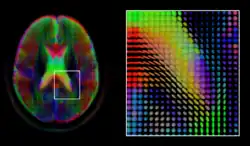

Diffusion MRI

Diffusion MRI is a structural magnetic resonance imaging modality that allows measurement of the diffusion process of molecules. Diffusion is measured by applying a gradient pulse to a magnetic field along a particular direction. In a typical acquisition, a set of uniformly distributed gradient directions is used to create a set of diffusion weighted volumes. In addition, an unweighted volume is acquired under the same magnetic field without application of a gradient pulse. As each acquisition is associated with multiple volumes, diffusion MRI has created a variety of unique challenges in medical image computing.

In medicine, there are two major computational goals in diffusion MRI:

- Estimation of local tissue properties, such as diffusivity;

- Estimation of local directions and global pathways of diffusion.

The diffusion tensor,[58] a 3 × 3 symmetric positive-definite matrix, offers a straightforward solution to both of these goals. It is proportional to the covariance matrix of a Normally distributed local diffusion profile and, thus, the dominant eigenvector of this matrix is the principal direction of local diffusion. Due to the simplicity of this model, a maximum likelihood estimate of the diffusion tensor can be found by simply solving a system of linear equations at each location independently. However, as the volume is assumed to contain contiguous tissue fibers, it may be preferable to estimate the volume of diffusion tensors in its entirety by imposing regularity conditions on the underlying field of tensors.[59] Scalar values can be extracted from the diffusion tensor, such as the fractional anisotropy, mean, axial and radial diffusivities, which indirectly measure tissue properties such as the dysmyelination of axonal fibers [60] or the presence of edema.[61] Standard scalar image computing methods, such as registration and segmentation, can be applied directly to volumes of such scalar values. However, to fully exploit the information in the diffusion tensor, these methods have been adapted to account for tensor valued volumes when performing registration [62][63] and segmentation.[64][65]

Given the principal direction of diffusion at each location in the volume, it is possible to estimate the global pathways of diffusion through a process known as tractography.[66] However, due to the relatively low resolution of diffusion MRI, many of these pathways may cross, kiss or fan at a single location. In this situation, the single principal direction of the diffusion tensor is not an appropriate model for the local diffusion distribution. The most common solution to this problem is to estimate multiple directions of local diffusion using more complex models. These include mixtures of diffusion tensors,[67] Q-ball imaging,[68] diffusion spectrum imaging [69] and fiber orientation distribution functions,[70][71] which typically require HARDI acquisition with a large number of gradient directions. As with the diffusion tensor, volumes valued with these complex models require special treatment when applying image computing methods, such as registration[72][73][74] and segmentation.[75]